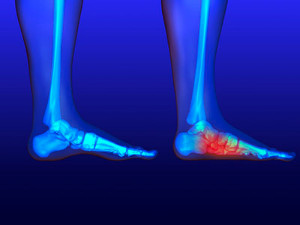

Flatfoot is a condition in which the arch of the foot is depressed and the sole of the foot is almost completely in contact with the ground. About 20-30% of the population generally has flat feet because their arches never formed during growth.

Having flat feet makes it difficult to run or walk because of the stress placed on the ankles.

Alignment – The general alignment of your legs can be disrupted, because the ankles move inward which can cause major discomfort.

Knees – If you have complications with your knees, flat feet can be a contributor to arthritis in that area.

- Pain around the heel or arch area

- Flat look to one or both feet

- Having your shoes feel uneven when worn

If you are experiencing pain and stress on the foot you may weaken the posterior tibial tendon, which runs around the inside of the ankle.